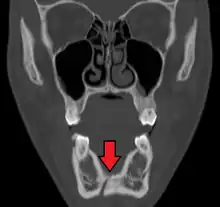

| 3D computed tomographic image of a mandible fracture in two places. One is a displaced right angle fracture and the other is a left parasymphyseal fracture. | |

Computed tomography

Computed tomography is the most sensitive and specific of the imaging techniques. The facial bones can be visualized as slices through the skeletal in either the axial, coronal or sagittal planes. Images can be reconstructed into a 3-dimensional view, to give a better sense of the displacement of various fragments. 3D reconstruction, however, can mask smaller fractures owing to volume averaging, scatter artifact and surrounding structures simply blocking the view of underlying areas.